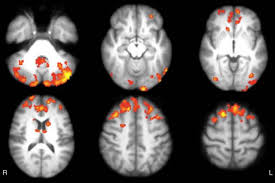

Remember, the brain is adaptable. Studies show gaming actually enhances neuroplasticity, bolstering areas like attention, vision, and motor control. In fact, research even explores therapeutic applications: for instance, video-game-based training boosts attention and functional brain connectivity in individuals with schizophrenia.